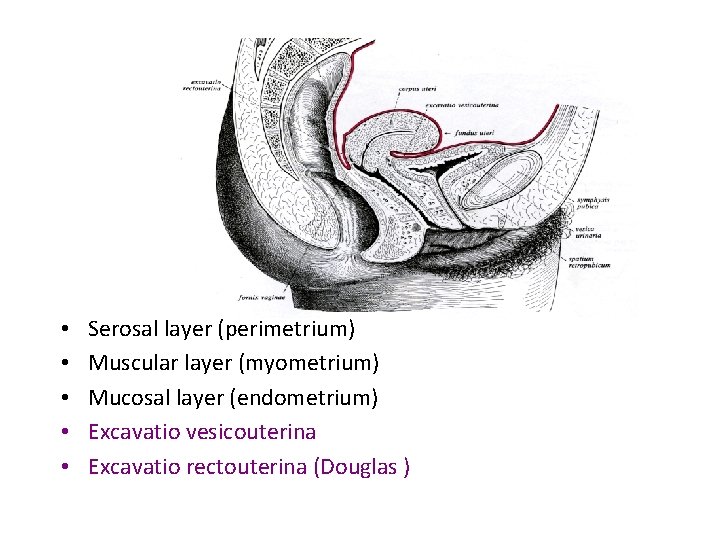

• • • Serosal layer (perimetrium) Muscular layer (myometrium) Mucosal layer (endometrium) Excavatio vesicouterina Excavatio rectouterina (Douglas )